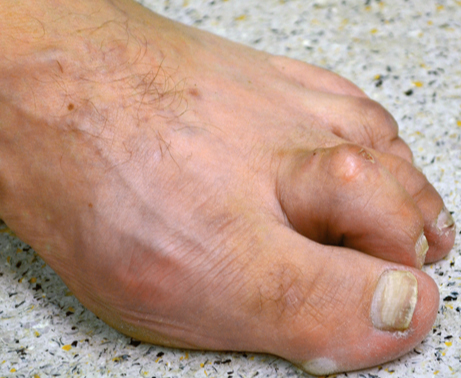

Claw Toe